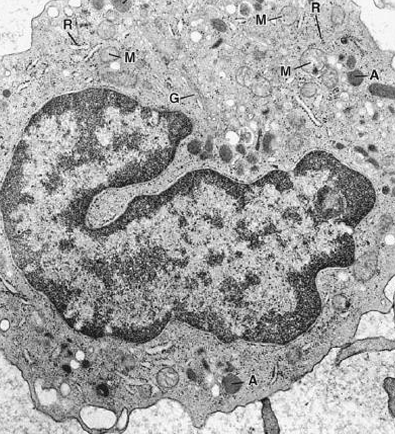

monocito

Qué es el Sistema Monocito–Macrofágico

Precursores médula ósea (monoblastos y promonocitos)

Monocitos circulantes

Macrófagos tisulares libres o fijos (histiocitos).